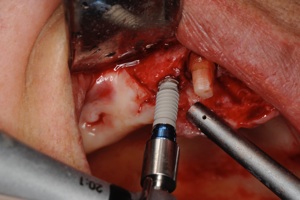

1.インプラントの手術 1,2時間程度で終わります。麻酔は局所麻酔です。

1次オペ

インプラント

埋入